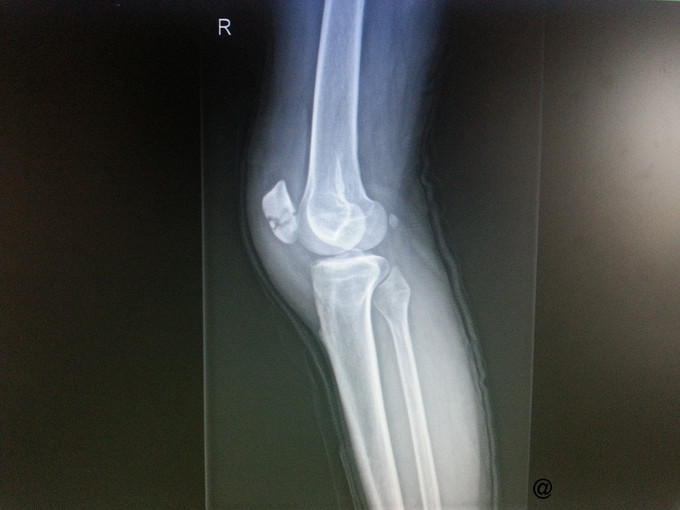

主诉:外伤致右膝疼痛、肿胀伴活动受限4小时 病史:患者四小时前骑车时不慎摔倒,右膝着地后出现疼痛,局部肿胀,压痛明显,右膝关节活动明显受限,皮肤稍有破损,无明显畸形,无瘀点瘀斑,右踝部及右脚趾活动正常。至我院急诊诊断:右髌骨骨折。为进一步治疗拟“右髌骨骨折”收治入院。 病程中患者神清,精神可,体温正常,胃纳夜眠可,二便无殊,体重无变化。

查体:右膝压痛明显,稍有肿胀,皮肤破损,无淤血斑块,主动被动活动受限;远端足背动脉可及搏动,右下肢远端、右踝、脚趾活动、感觉及皮温与左健侧基本相同。 辅检:X片提示右髌骨骨折。

诊断:右髌骨骨折 处理:右髌骨骨折切开复位克氏针内固定术

患者术后2周可以屈膝超过90°。手术切口愈合好。 髌骨骨折早期应在支具的保护下下地行走。康复训练应包括一次极限的屈膝练习。请讨论无移位的髌骨骨折是否需要内固定